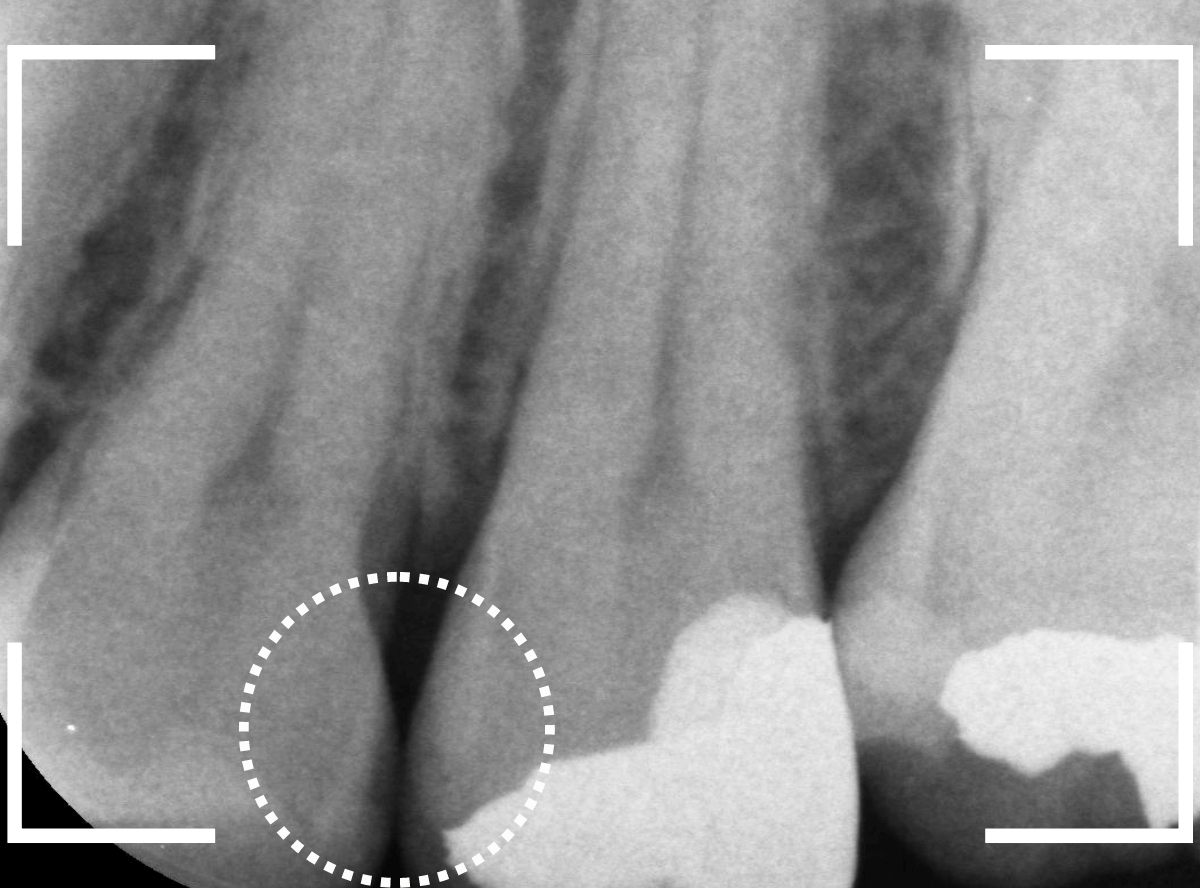

Case.18 虫歯なのは間違いないが、境界がはっきりしない

「つめものが外れて、噛むと痛い」という訴えで来院された患者さんさんです。

一見で、表面が虫歯になっているのと、レジンが劣化しているのがわかります。

レントゲン写真で確認します。

〇部が当該の歯です。

症状もあるので、虫歯が深そうですが、全体がもやっとして、どこからどこまで虫歯なのかはっきりわかりません。

まれに、こんな時もあります。

レジンを外し、虫歯の処置を進めます。

慎重に虫歯を除去し、一安心か、という寸前で(〇部、小さく出血しているところ)露髄してきました。

神経を除去しないとダメかもしれません。。。

神経を保護するお薬をつめて、経過観察します。

痛みが出ませんように。。。